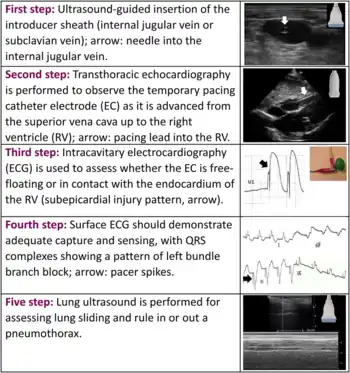

| Steps | 1) Place a sheath introducer in the right IJ 2) Check the device balloon 3) Attach sleeve to the hub of the introducer 4) Insert device about 20 cm through the hub 5) Connect to the energy generator 6) Set the generator at 80 BPM and 20 mA 7) Inflate the balloon and advance into the right ventricle (wide QRS complex is seen) 8) Adjust the generator to lowest effective mA 9) Deflate the balloon, secure the sleeve and sheath[3][2] |

- The first step is placing a sheath introducer.[1] Usually this is a 6 Fr and most catheter electrodes are 5 Fr.[2] This is generally done in the right internal jugular vein.[3]

- To check the balloon on the device, inflate with 1.5 ml of air and than deflate.[3]

- A sterile sleeve is attached to the hub of the sheath.[3]

- Insert the device about 20 cm (to the 2 black lines) through the hub and sleeve with the coil of the tip to the persons left.[3]

- Connect the device to the energy generator and turn the generator on.[3] The positive electrode goes into the positive connector terminal and the negative electrode goes in the negative connector terminal.[2]

- Set the generator to 80 BPM and the output to 20 mA.[3][2] The sensitivity should be set to asynchronous / lowest sensitivity number.[2]

- Inflate the balloon and advance the pacer into the right ventricle.[3] This will appear as pacer spikes and a wide QRS complex on the monitor.[3]

- Adjust the generator output to the lowest effective mA.[3] Decrease the rate to 60 BPM.[2] Sensitivity can also be increased.[2]

- Deflate the balloon and secure the sleeve and sheath into place.[3]

The pacing device may also be advanced through the vein under electrocardiography (ECG) or ultrasound guidance.[1][3] Before pulling back the device make sure the balloon is deflated.[2]

Ultrasound showing the device in the right ventricle

Ultrasound showing the device in the right ventricle The device inappropriately passing into the inferior vena cava

The device inappropriately passing into the inferior vena cava Setup for doing an ECG off the device

Setup for doing an ECG off the device Example of ECG off the device a) free floating in the RV b) in contact with the RV wall

Example of ECG off the device a) free floating in the RV b) in contact with the RV wall It is possible to place the lead in the coronary sinus, normal (left) dilated (right). Such placement is okay.

It is possible to place the lead in the coronary sinus, normal (left) dilated (right). Such placement is okay.